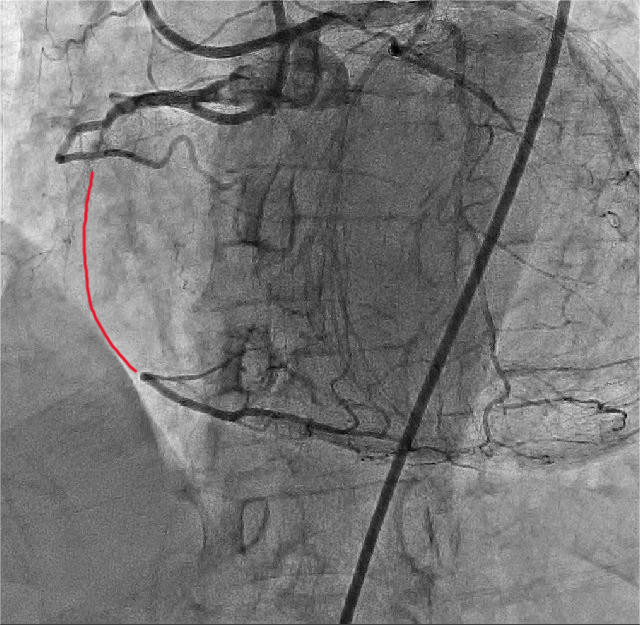

4月19日,手术团队对该患者开展冠状动脉造影检查。造影结果提示:右冠状动脉中段闭塞病变,前后降和回旋支开口狭窄50%,前降支动脉通过新生血管向右冠状动脉形成侧枝血供。朱舜明副主任医师向患者和家属告知病情严重性,为保证手术安全,建议其择期行逆向冠脉病变治疗术或保守治疗。两难抉择下,患者家属仍考虑择期采用新技术开通闭塞血管。手术团队再次分析患者病情并制定详细方案:拟择期采用Reverse-CART通过前降支侧枝血管逆行开通闭塞右冠状动脉。

图1 股动脉和桡动脉双路径造影提示:右冠状动脉中段闭塞病变,红色线条:闭塞血管段。